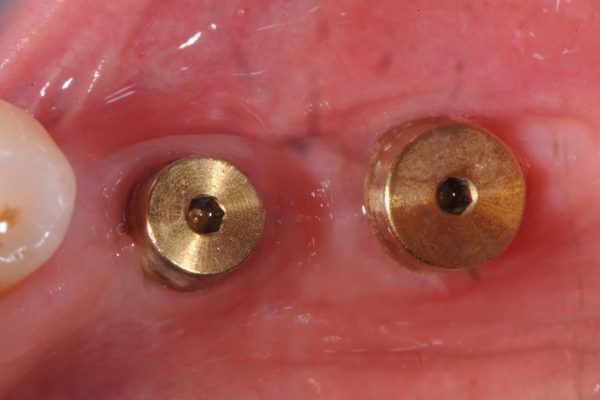

Importante perdita ossea Verticale ed orizzontale provocata dalla perdita di Impianti posizionati a causa della MANCANZA di una attenta diagnosi, piano di trattamento e capacità operativa, che avrebbero mostrato l’impossibilita di posizionare gli Impianti senza ripristinare lo spessore osseo adeguato …